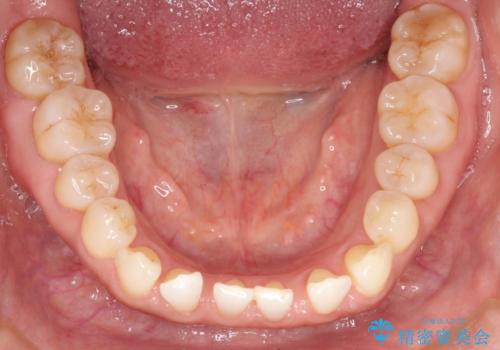

前歯の隙間 インビザラインによる目立たない成人矯正

- 前歯の隙間を気にされて来院されました。

インビザラインにて、目立たずに矯正治療を行うこととしました。

歯と歯の間にある隙間を閉じるのは、インビザラインでもしっかり治療できます。